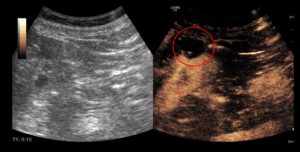

Bild: Kontrastmittelverstärkte Sonografie. Im linken Bild sieht man das klassische Sonografiebild der linken Niere mit einer Zyste am Oberrand (dunkler Fleck). Im rechten Bild zeigt die Kontrastdarstellung (bräunlich) die leere Zyste mit einer kontrastmittelaufnehmenden Struktur am Zystenrand bei 7 – 9 Uhr. Der Befund wird in drei Monaten kontrolliert und ggf. muss die Zyste dann minimalchirurgisch entfernt werden.